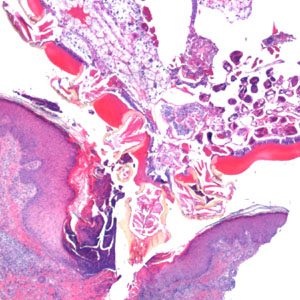

An 81-year-old man, with a previous history of basal-cell carcinoma on his upper right arm and shoulder, presented with a small protuberance in the hollow of his left knee. A biopsy specimen was collected, sectioned, and stained with hematoxylin-and-eosin (H&E). Figures A–D show what was observed by the attending pathologist. What is your diagnosis? Based on what criteria?

Figure B